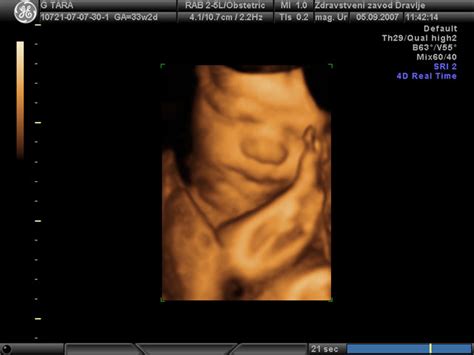

Tri- in štiridimenzionalni ultrazvok: Vizualizacija v novi dimenziji

Poleg standardnega dvodimenzionalnega (2D) ultrazvoka, ki daje črno-bele prereze, obstajata tudi 3D in 4D ultrazvok.

- 3D ultrazvok: Ta tehnika ustvari tridimenzionalno računalniško rekonstrukcijo slike iz serije zaporednih 2D slik. Omogoča boljše merjenje volumnov in prikazovanje telesnih značilnosti ploda v prostoru, kar staršem pomaga pri boljši predstavi o videzu otroka.

- 4D ultrazvok: Dodaja časovno komponento k 3D sliki, kar omogoča opazovanje gibanja ploda v realnem času.

Čeprav 3D/4D ultrazvok ponuja vizualno bogatejše izkušnje, njegova diagnostična vrednost v primerjavi z 2D ultrazvokom ni vedno bistveno večja, razen pri določenih specifičnih ocenah. Pogosto se uporablja za prikazovanje določenih delov plodovega telesa staršem. Zavedati se je treba, da so ti pregledi pogosto samoplačniški.